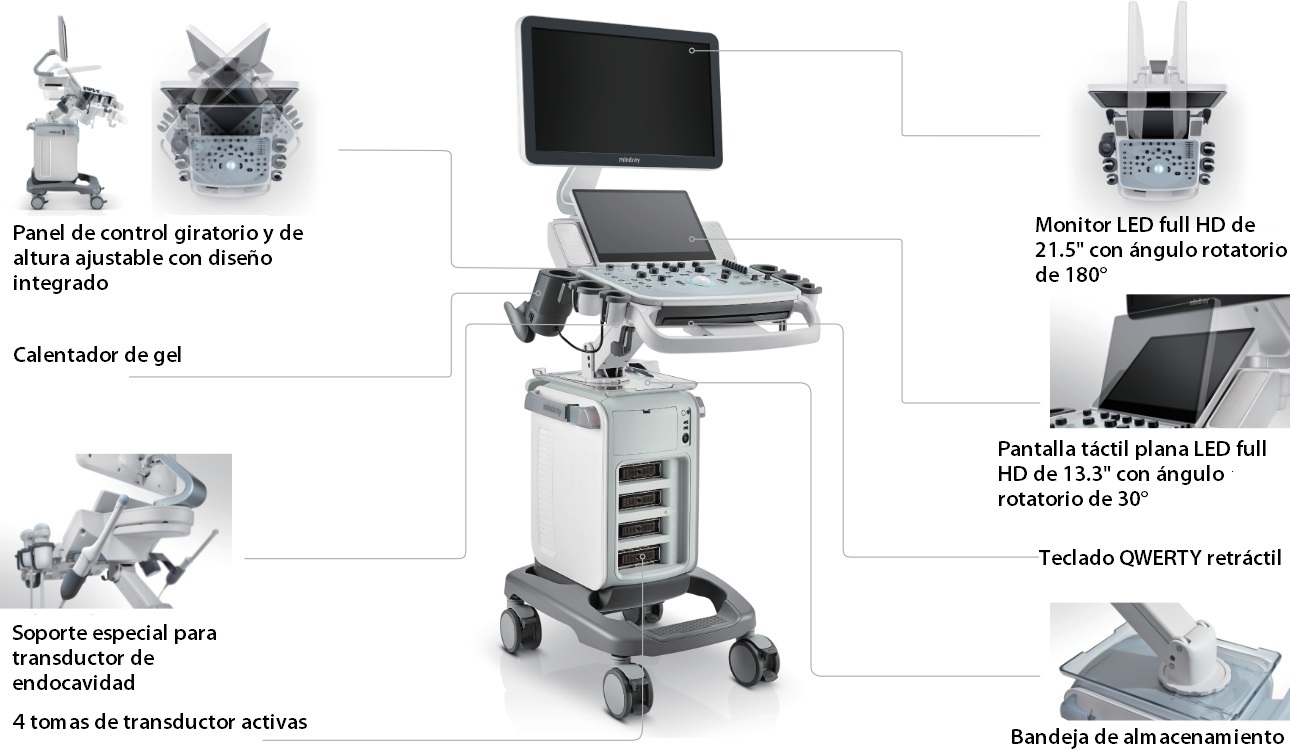

DescripciĂłn general

Dise?o ergonĂłmico mejorado

MĂĄs cĂłmodo de usar

Gama completa de herramientas de aplicaciĂłn: garantĂa de precisiĂłn con comodidad

iTouch

DC-40 con Full HD ofrece una gama de herramientas que maximizan la precisiĂłn del diagnĂłstico con comodidad. DC-40 con Full HD le brinda una soluciĂłn completa para aplicaciones clĂnicas convencionales, con un flujo de trabajo simplificado que garantiza la eficiencia y permite realizar escaneos generales, de ginecologĂa, obstetricia y cardiologĂa.